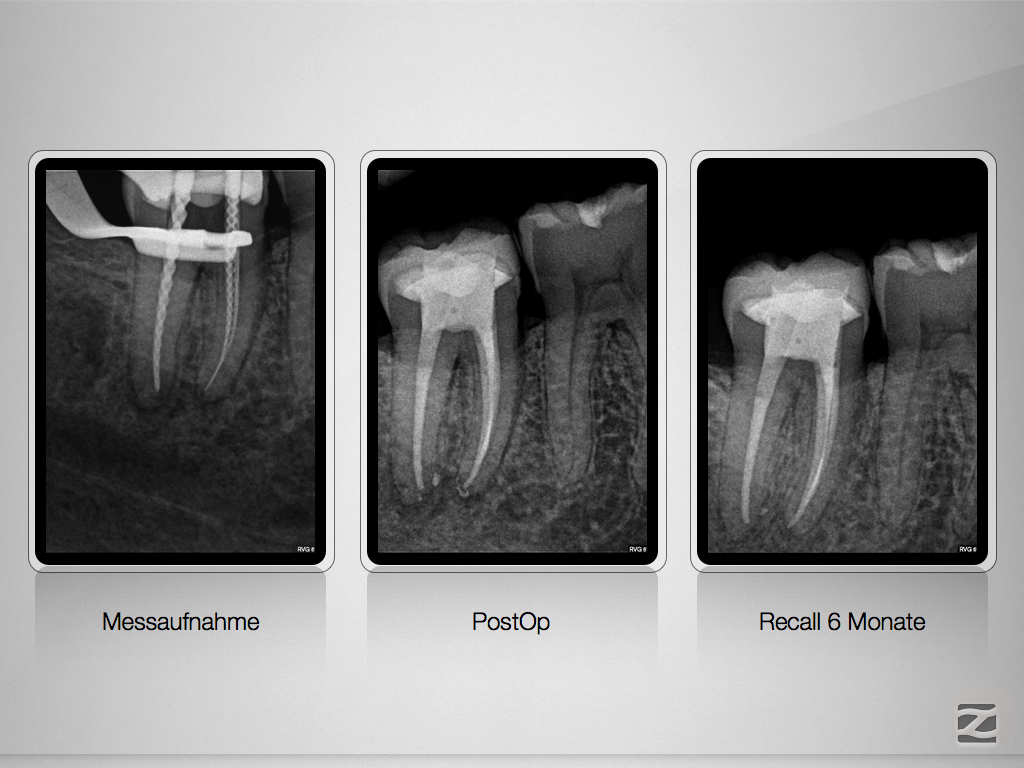

41-42-d-006

Ja ist denn schon Weihnachten?